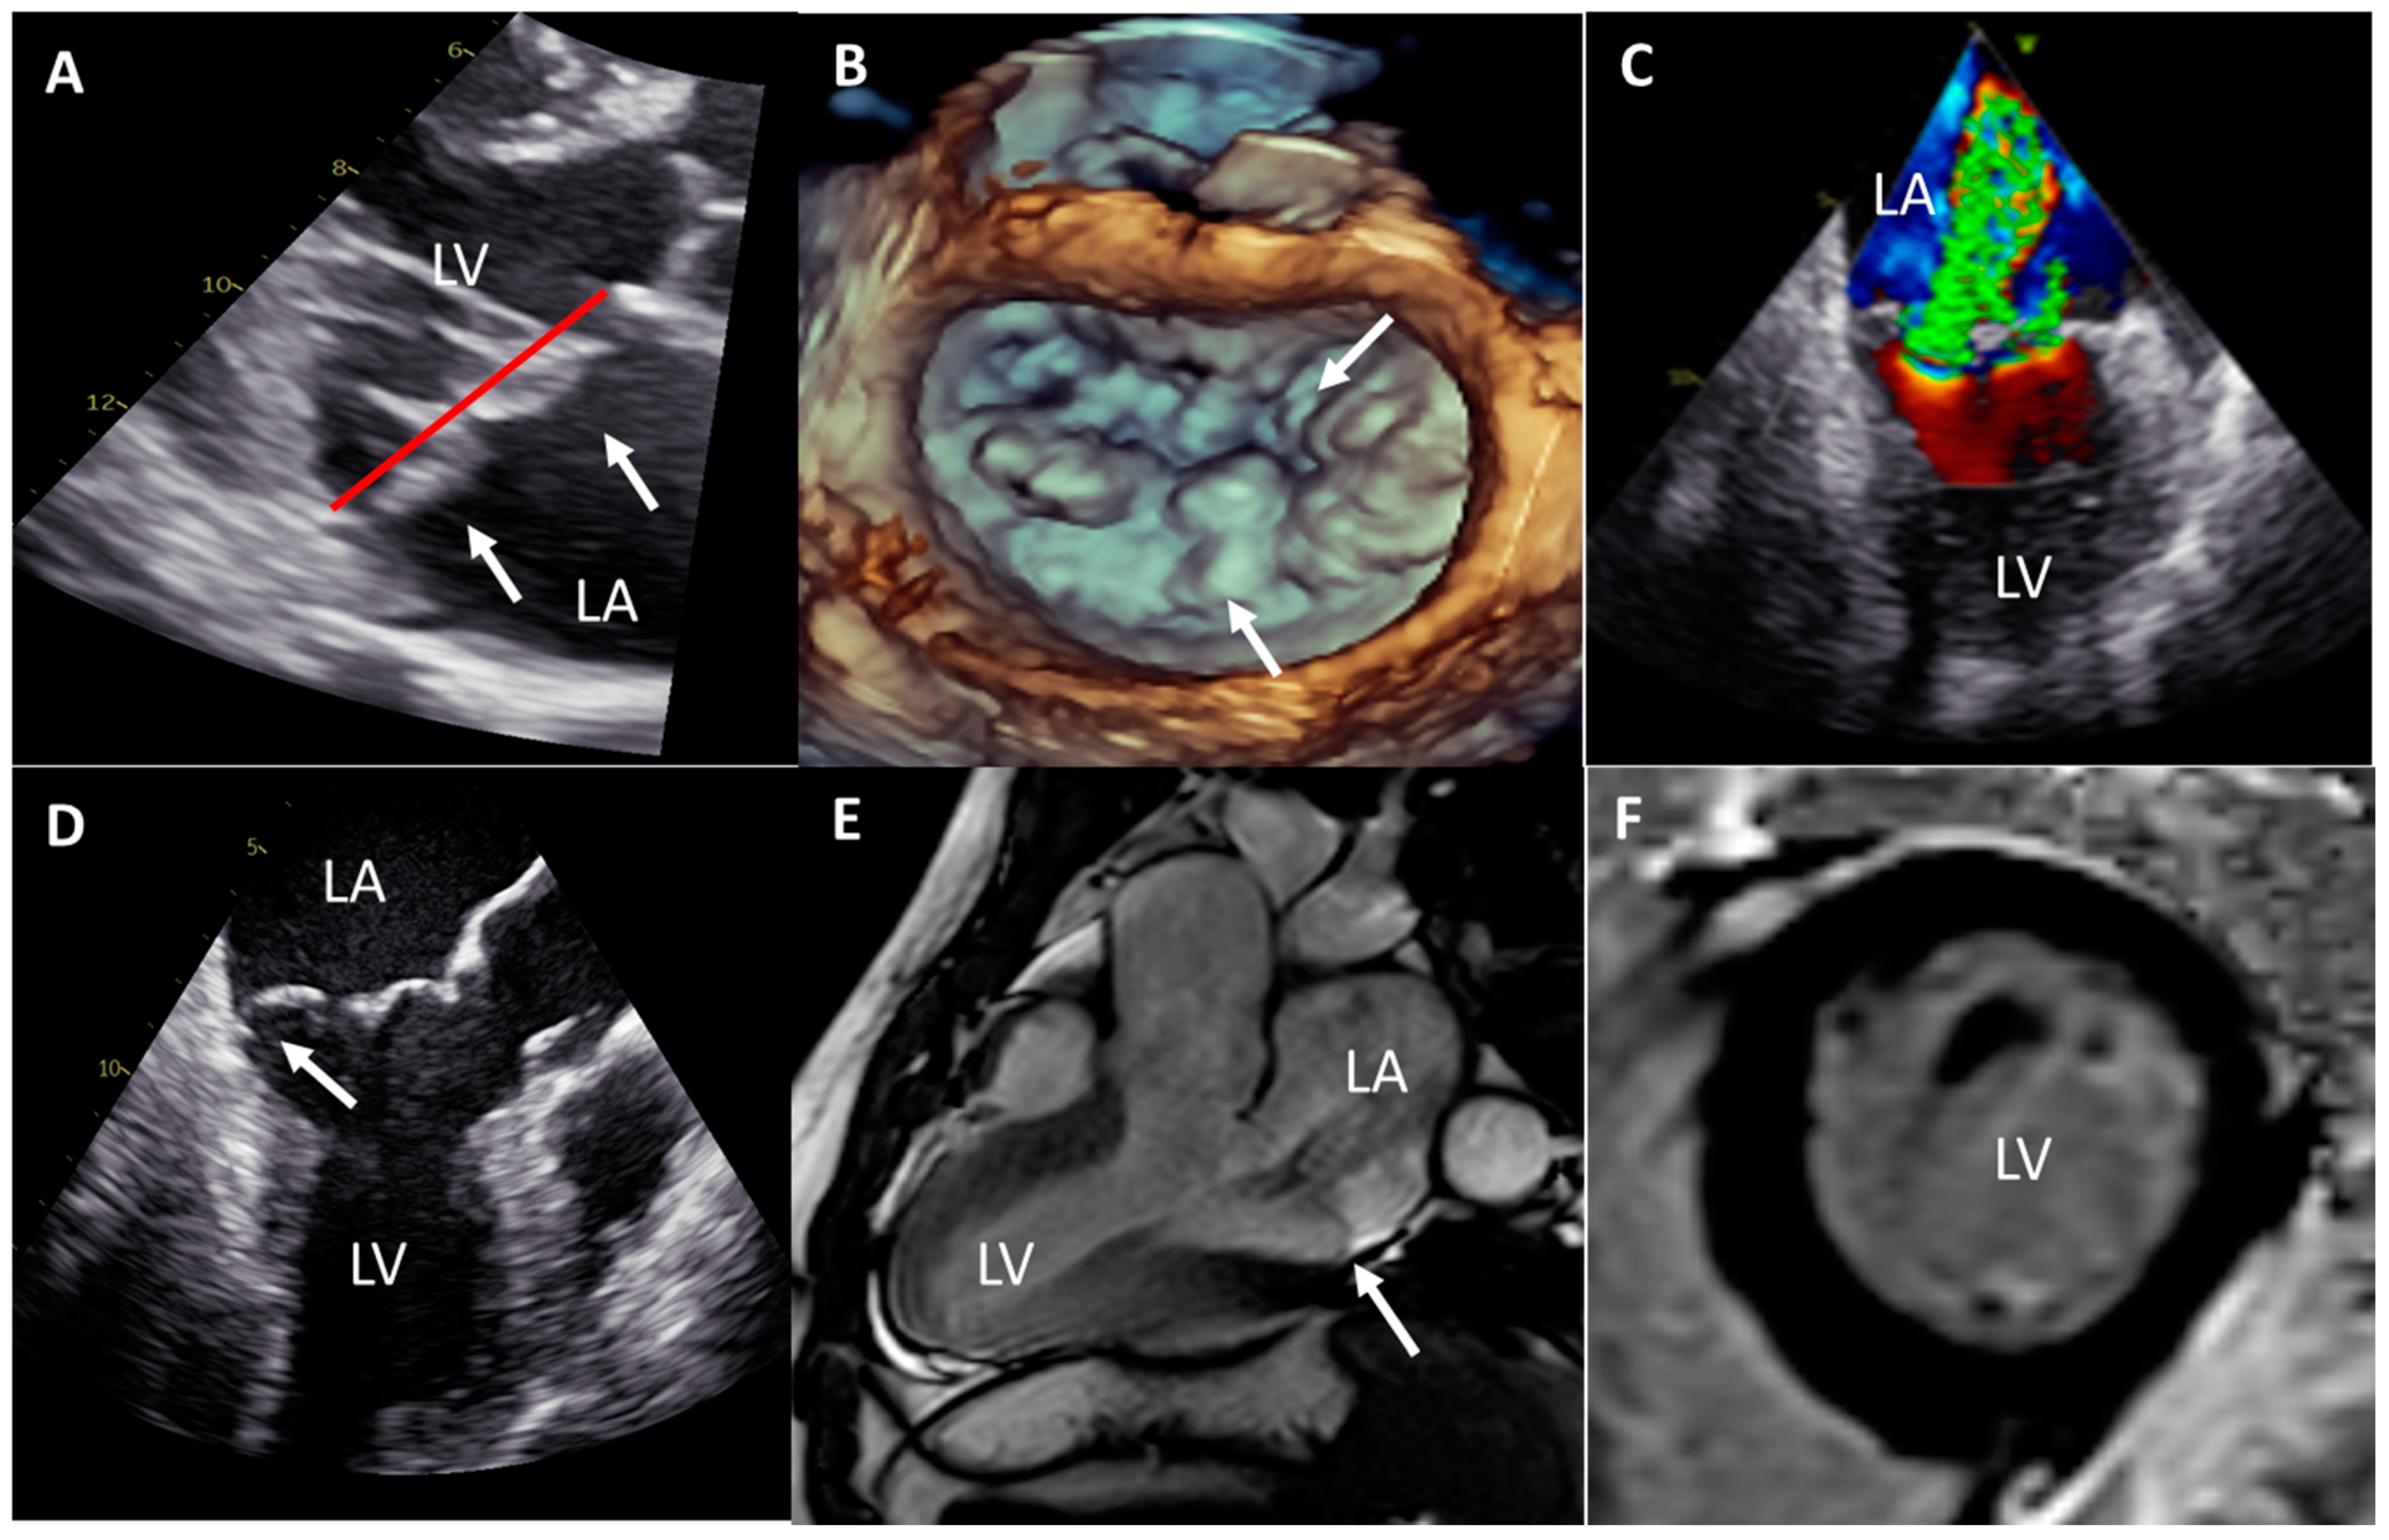

2. Case Report